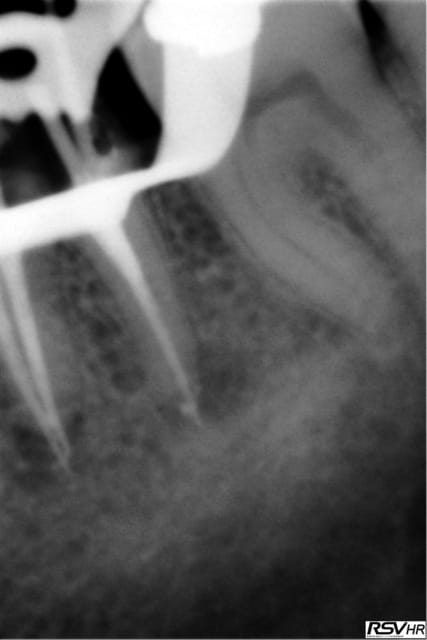

UN exemple de RTE

dépose inlay+couronne en 2009

retraitement sous digue indispensable(même sur dents antérieures la digue ce n'est pas pour faire jolie,c'est pour permettre à l'hypochlorite de rester à demeure tout le long du retraitement;il faut que çà "baigne" pour avoir une chance de

guérison apicale)

ici traitement sous hypo+digue +r-endo;il y a un dépassement léger au périapex

en 2015 guérison apparente du périapex(1h30 de retraitement!)

la dépose de l'inlay avec des ultrasons;désobturation acétate éythyle r-endo gutta compactage mac spadden

5eme photos en2009 et 2010;la dernière en 2015